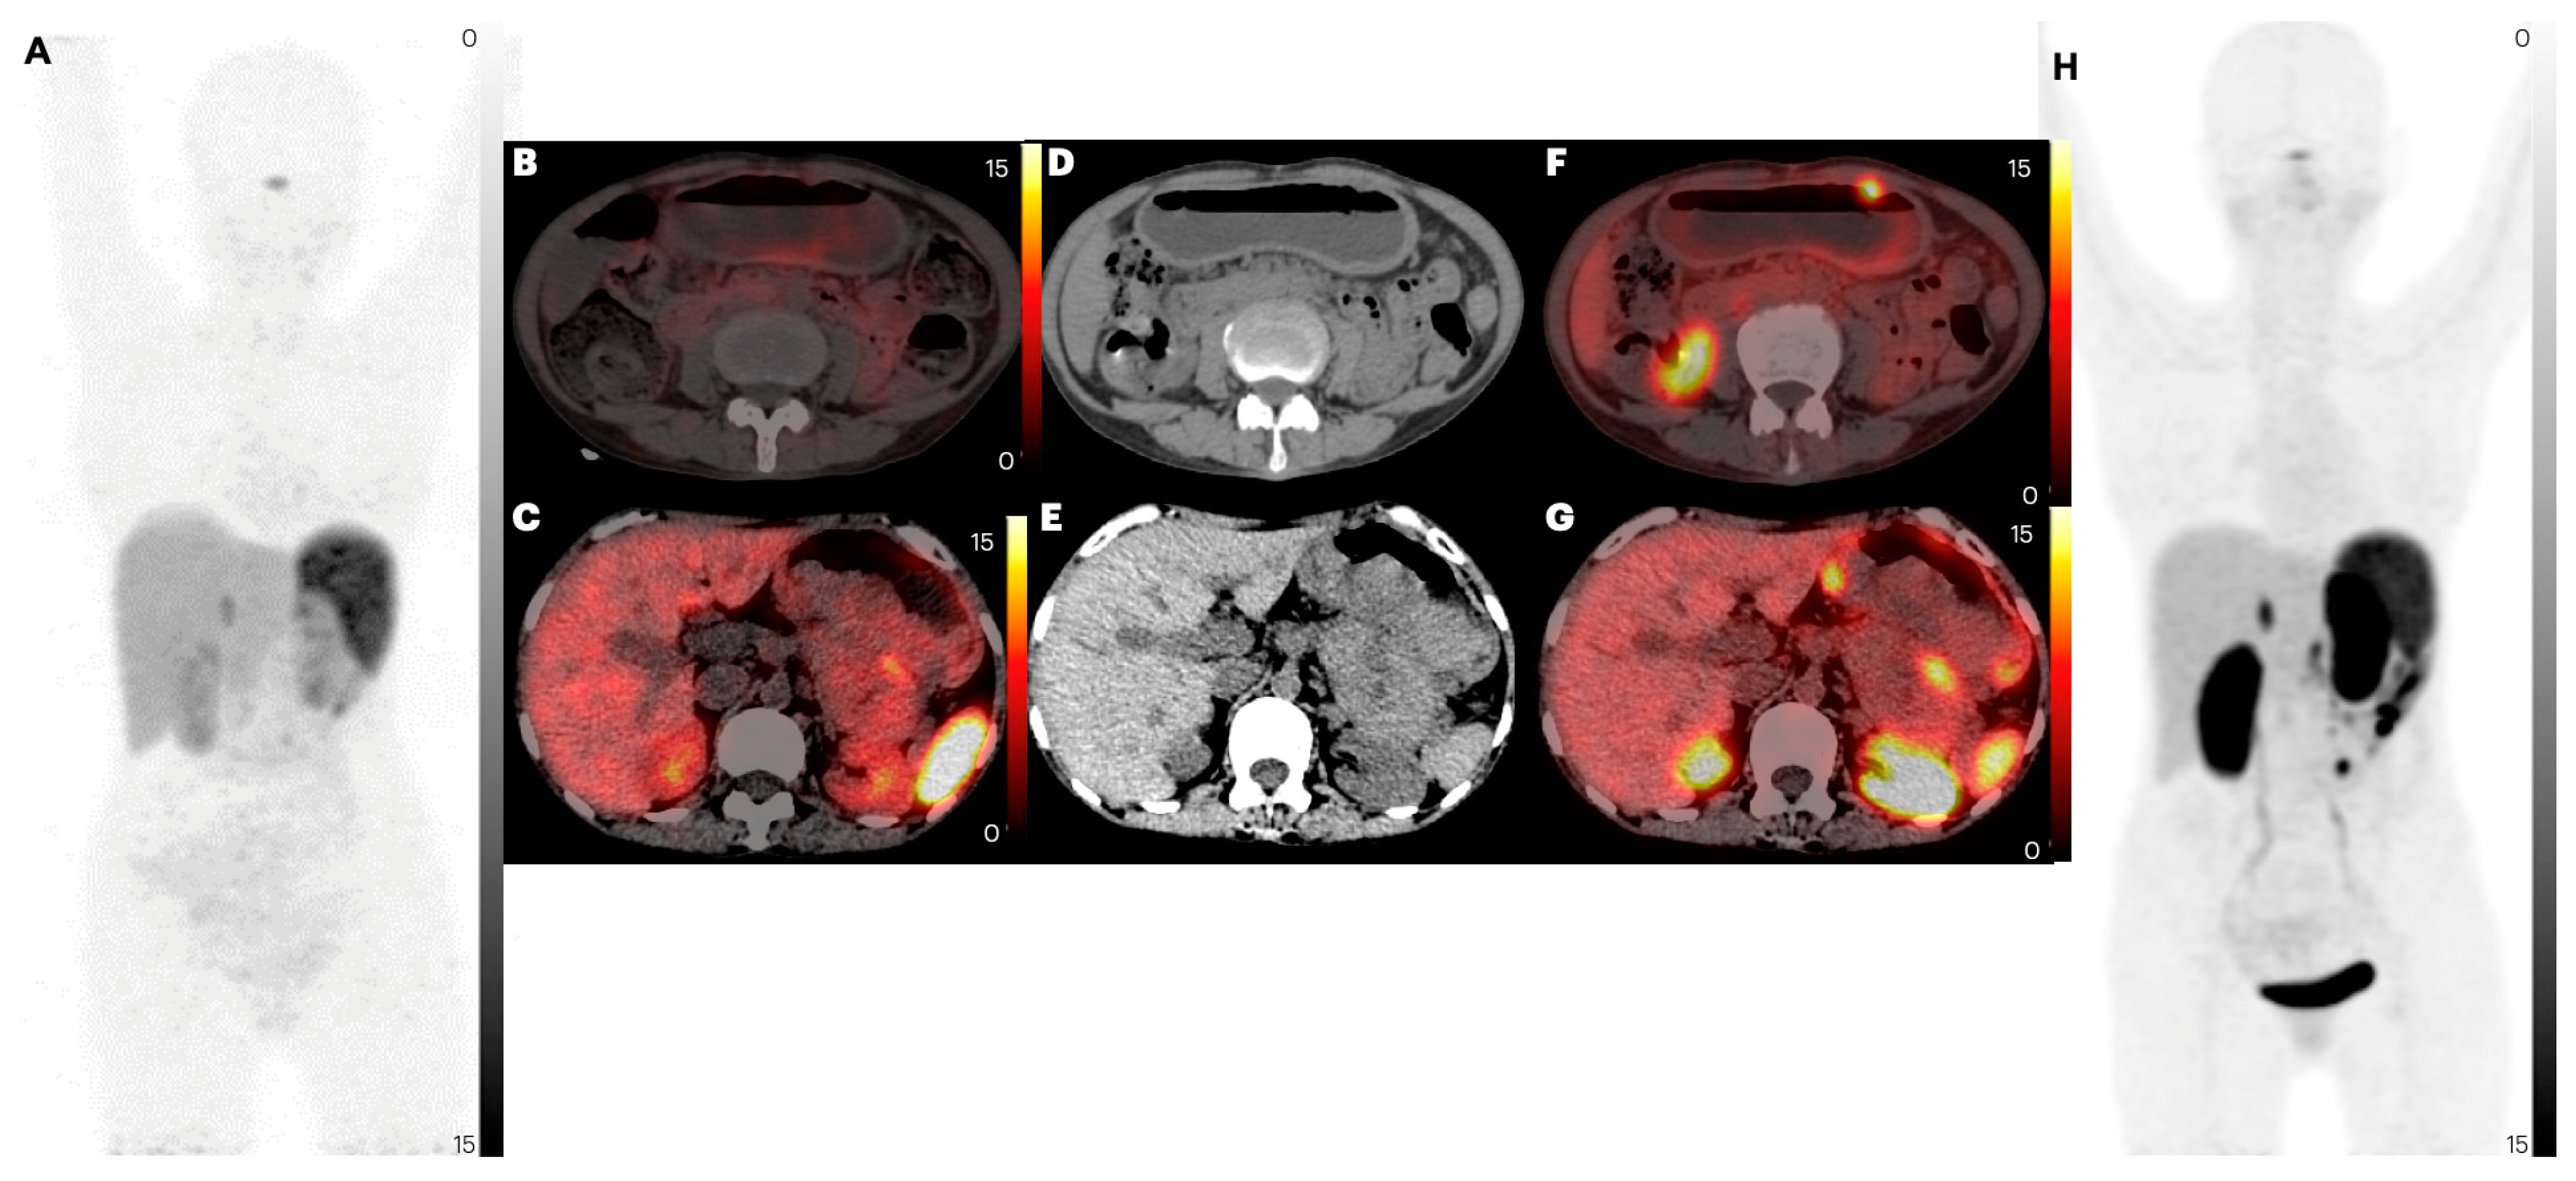

2.2.2. Lymph Node Metastases

2.2.5. Bone Metastases